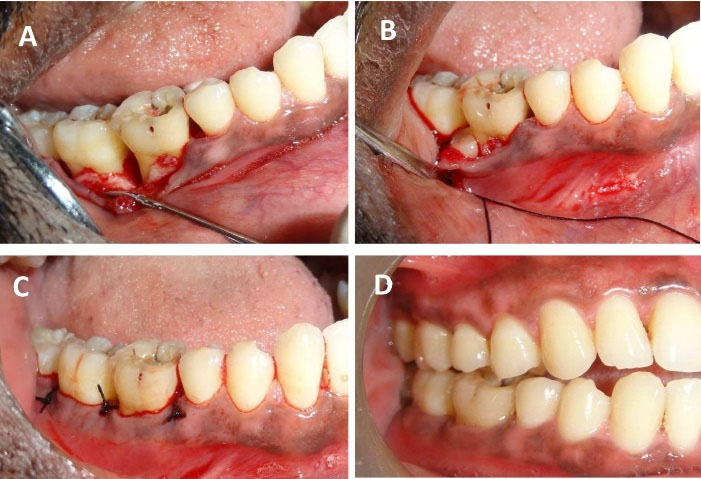

After anesthetizing with 2% lignocaine containing 1:80,000 adrenaline (Lignox A 2%, Indoco Remedies LTD., India) using the inferior alveolar nerve block. We placed sulcular incisions on both buccal and lingual sides and reflected a full-thickness mucoperiosteal flap extending from the mesial of the lower right second premolar (#45) to the mesial line angle of the lower right third molar (#48). Thorough debridement of granulation tissue in the intrabony defect (3-wall defect between #46 and #47 and #47 and #48 regions), scaling, and root planing of remnant calculus on the root surfaces was performed (Figure 3). After pre-suturing of the interdental papillae in the #46, #47, and later in #47 and #48 regions, the freshly prepared PBMSCs + PRFM was extracted en masse from the glass vial with the help of tweezers and filled into the intrabony defect as a sole material. The flaps were approximated by interrupted sutures using 4-0 silk material (Figure 3). No periodontal dressing was applied. Antibiotics (Amoxycillin 500 mg every 8 hours for 7 days) and analgesics (Ibuprofen 400 mg every 4 hours) as required for pain management were prescribed. 0.2% chlorhexidine rinses every 12 hours for 14 days were advised. Postoperative instructions were given, an ultra-soft toothbrush was prescribed, and the patient was advised to refrain from disturbing the surgical site for the next two days.

Figure 3.

Surgical procedure and post-surgical illustrations. (A) A mucoperiosteal flap was reflected, and surgical debridement was performed. (B) PBMSCs + PRFM en masse was placed in the intrabony defect. (C) Interrupted sutures were placed to approximate the flap. (D) Three-month postoperative follow-up displaying complete soft tissue healing

The patient was followed for one month after endodontic treatment with no evident changes in the clinical parameters; hence, we proceeded to surgical therapy. We also conducted post-surgical follow-up after a week, one month, 3 months, and 9 months. During the first follow-up appointment, the patient had no complaints of pain and discomfort and no tenderness on percussion. We reinforced oral prophylactic instructions. The sutures were removed ten days after surgery. During the one-month and three-month appointments, the patient displayed good oral hygiene. The surgical area displayed complete healing, no tenderness on percussion, and no tooth mobility. Radiographic evaluation three months after surgery displayed a partial bone fill (Figure 1). During the 9-month follow-up appointment, the periodontal lesion had significantly improved clinically and radiographically (Figures 1 and 3). A significant reduction in the periodontal probing depth and gain in the clinical attachment level was noted (Table 1). At any of these intervals, there was no attempt at subgingival instrumentation.